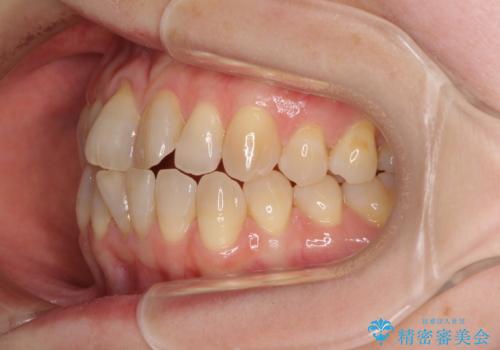

前歯の叢生と切端咬合 インビザラインによる矯正治療

- 前歯のデコボコを気にして来院された患者様です。

上下前歯の先端同士が接触する切端咬合であったため、上顎は歯列を拡大し、下顎はIPR(歯と歯の間を削る)により叢生を解消しながら歯列を小さくすることとしました。

治療前から歯肉退縮が認められ、矯正治療により悪化する可能性が考えられたため、無理のない歯の移動と頻繁な経過観察を行いました。

切端咬合はスムーズに解消され、前歯の負担を軽減させることができました。